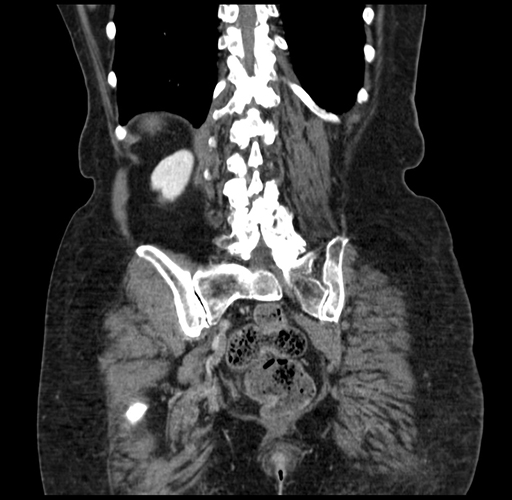

Pre-Chemo: Coronal Venous

Coronal Venous